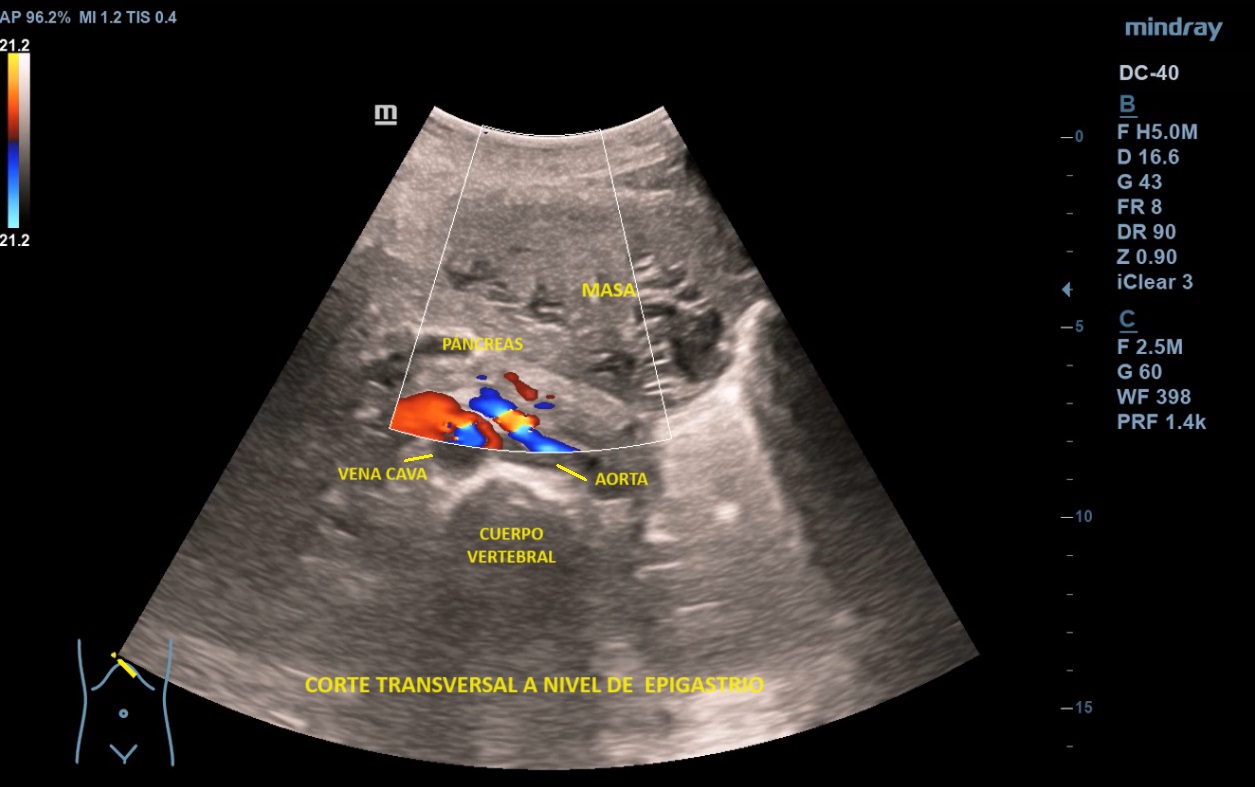

Ecografía abdominal clínica: Masa heterogénea que ocupa todo el abdomen, de aspecto sólido, vascularizada con zonas hipoecoicas-anecoicas en su interior. Riñones con eco-estructura sin alteraciones, hígado sin LOES. Vejiga sin engrosamiento de paredes, útero parcialmente visible. Anejos y retroperitoneo no valorables. No líquido libre.

Los leiomiomas uterinos son el tumor más frecuente de pelvis en la mujer. La ecografía es la primera línea de estudio. Habitualmente s

e describen como masas bien delimitadas redondeadas hipoecoicas con sombra acústica, aunque también pueden tener áreas isoecoicas e hiperecoicas. Pueden presentar necrosis central (áreas anecoicas) o calcificaciones, sin implicar malignización. El Doppler-color suele mostrar una distribución irregular de los vasos. El diagnóstico definitivo es el anatomo-patológico.